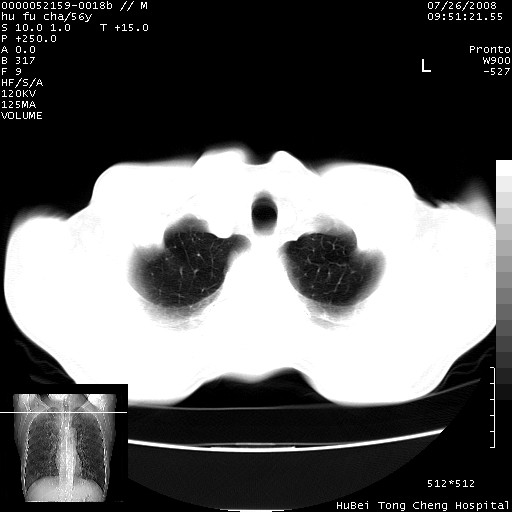

以下是引用zsl6918在2008-8-25 22:47:00的发言:[br]胸骨,胸椎及肋骨均可见多发转移表现,肝内低密度结节不除外转移。原发灶可能在右肺。双侧可见支扩表现。

以下是引用卜一在2008-8-26 8:02:00的发言:[br][br] 支持:肺癌并肺内,胸骨,胁骨,胸椎及肝内转移!另:左肺支气管扩张征伴感染! [br]

以下是引用zjzjr在2008-8-26 11:03:00的发言:[br]支持:肺癌并肺内,胸骨,胁骨,胸椎及肝内转移!另:左肺支气管扩张征伴感染!